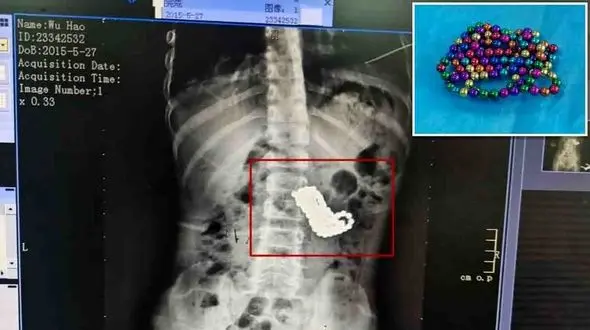

حوادث رکنا:سهل انگاری والدین چینی در خرید اسباببازی نامناسب برای کودک خردسالشان حادثهساز شد.